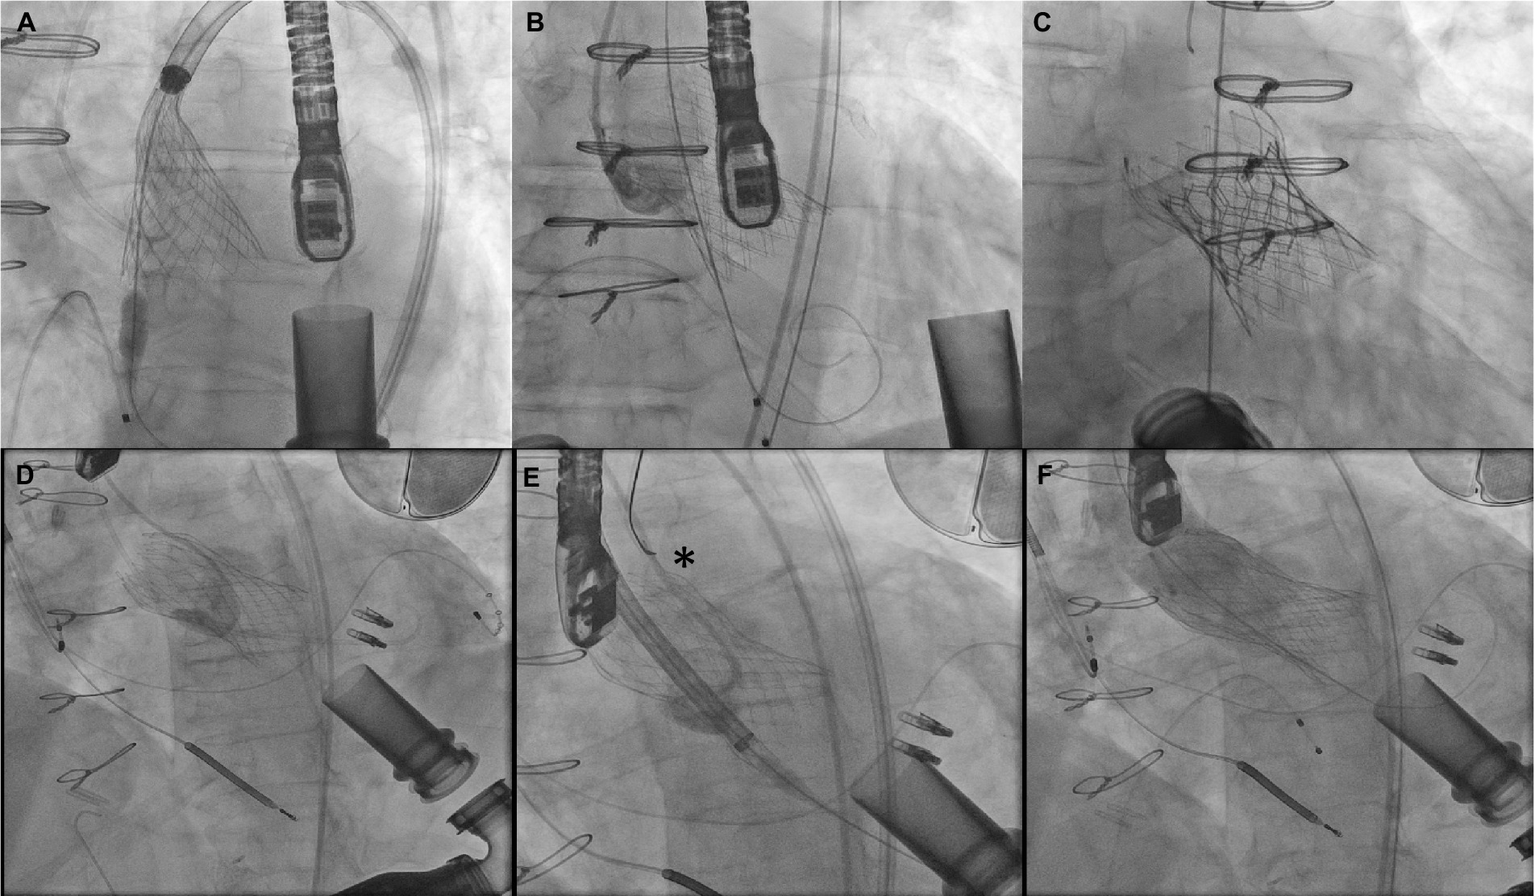

More cases have been reported with use of self-expanding valves, with the older generation as well as more current valve iterations. Use of a stiff wire for delivery is generally recommended with the Lunderquist double curve wire being commonly used. Oversizing with a range close or slightly over 30% is essential. The theoretical benefit of using a self-expanding platform is being able to recapture and test the valve in a 75–80% deployed state for longer durations of time to test stability. Longer pacing runs to allow the valve to expand more and stabilize are recommended. Still, valve migrations are common, hence being prepared to stabilize/pull up the valve with a single/double snare technique is required (62). Additional 6F accesses are required for this purpose and a double snare theoretically has a greater chance of successfully repositioning the valve and reduce the risk of aortic injury since the valve frame is compressed by pulling forces on the tabs from either side. The other approach is to place a second valve, usually a balloon expandable Sapien valve using the Corevalve/Evolut as a scaffold (Figure 9). However, this does not work for valve frames that are extremely deep.

Figure 9

(A–C) Attempted Evolut R implant with ventricular migration immediately after release stabilized with 29 mm Sapien 3 implant inside the malpositioned Evolut. (D–F) Ventricular migration of Evolut R valve in another patient with repositioning using a gooseneck snare (asterisk) and implantation of a second Evolut R inside with post dilation reducing aortic insufficiency to trace.

The first report of TAVR to treat LVAD associated AI was made by Santini et al. in 2012 (64). In what has been seen in other series that followed, the first Core valve that was deployed was not stable and had at least moderate perivalvular leak. A second Core valve was deployed inside the first one leading to an improved outcome, albeit still with mild peri-valvular leak. More reports of TAVR for LVAD AI have used self-expanding valves. Yehya et al. have reported the largest series with 6 months follow up (65). In two of the nine patients, there was acute valve migration into the LV necessitating snaring of the valve to correct the position and deployment of a second valve (one Sapien 3, one Core valve). One patient died 4 months after TAVR. There was no significant AI in the remaining eight patients at 6 months. Four of these TAVR valves appeared completely closed. There was improvement in RV function and tricuspid regurgitation and a median NYHA II functional class was maintained. This and other early reports include TAVR with first generation of self-expanding valves. The newer iteration of the Evolut platform including a 34 mm valve is a more intuitive choice in order to achieve greater oversizing and more radial force on the non-calcified annulus. Dhillon et al. report a series of four such cases using the 34 mm Evolut valve (66). Three of their cases were uncomplicated, however the fourth had significant ventricular migration which was managed with implantation of a 29 mm Edwards Sapien 3 valve in the waist to try and post dilate/stabilize the valve. The patient continued to have mild–moderate perivalvular leak, eventually had fusion of the valve leaflets and was not able to be rescued. Two of the other three patients also did not survive to 3 months. In a retrospective multi-center study evaluating TAVR for native AI, newer generation valve systems like the Evolut had significantly less chance of having a malposition and greater than moderate leak compared to first generation Core valve (67).